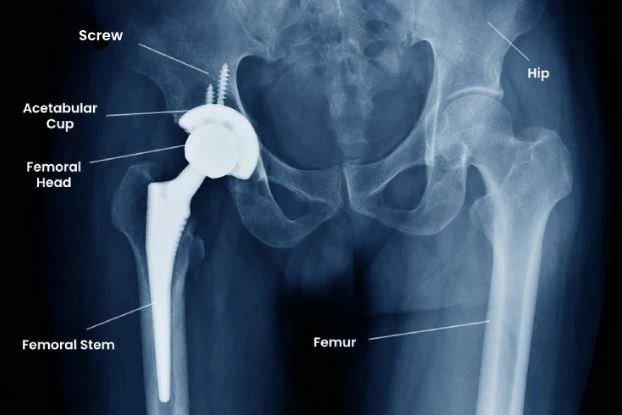

Total hip replacement is a procedure in which a damaged hip joint is replaced with artificial components, typically consisting of a metal stem, a ceramic or metal ball, and a polyethylene or ceramic socket. During our conversation, Dr Ponnanna emphasized that surgery is usually considered only after conservative measures—such as medication, physiotherapy, and lifestyle modification—fail to provide relief.

Common indications include severe osteoarthritis, rheumatoid arthritis, avascular necrosis of the femoral head, and certain fractures. In cities with aging populations and active lifestyles, Total Hip Replacement surgery in Bangalore has become increasingly common as patients seek durable solutions for chronic pain and mobility loss.